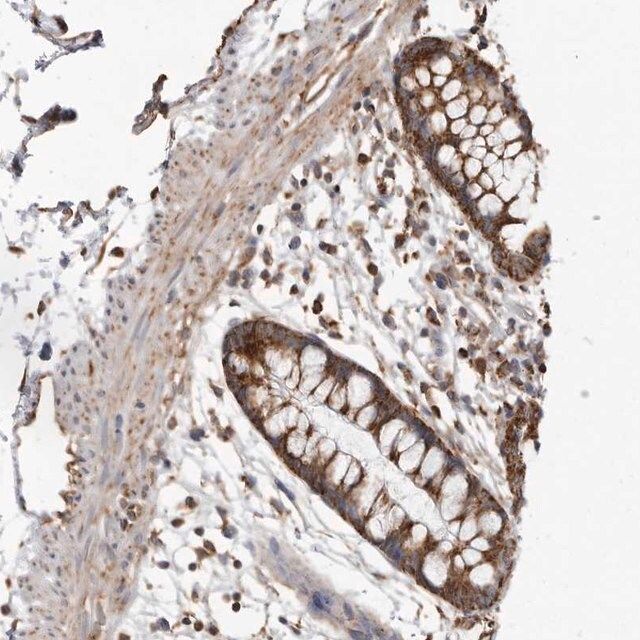

| Human Protein Atlas Number【人类蛋白质图谱编号】 | HPA027341 Human Protein Atlas characterization data |

| General description【一般描述】 | The gene FH (fumarate hydratase) is mapped to human chromosome 1q42.3-q43. The encoded protein is responsible for the conversion of fumarate to malate in the TCA (tricarboxylic acid) cycle. Fumarate is an oncometabolite and mutation in the FH gene causes accumulation of fumarate. Mutations in this gene are associated with HLRCC (hereditary leiomyomatosis and renal cell cancer) syndrome. Some mutations also cause fumarase deficiency resulting in neurological impairment. |

| technique(s) | immunoblotting: 0.04-0.4 μg/mL immunohistochemistry: 1:1000-1:2500 |